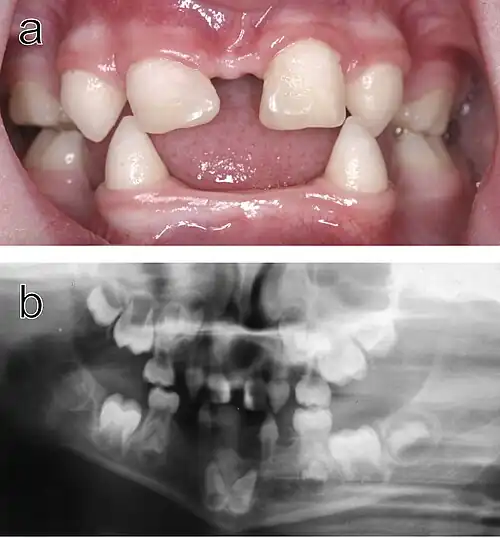

a) Intraoral view. Note that the upper incisors have been restored with composite material to disguise their original conical shape.

b) Orthopantomogram showing absence of ten primary and eleven permanent teeth in the jaws of the same individual.

Dental anomalies are among the most recognizable features of ED, with common findings including hypodontia (missing teeth), oligodontia (absence of six or more teeth), and anodontia (complete absence of teeth). Teeth that are present often exhibit unusual shapes, such as conical or peg-like forms, particularly in the anterior regions of the mouth. Delayed tooth eruption and other structural defects, such as taurodontism (enlarged pulp chambers), are also frequently observed.[1][3] These dental issues often necessitate early and prolonged dental treatments, including prosthodontics (dentures) and orthodontics (braces).[2]